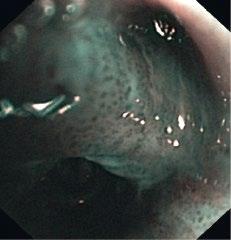

As autofluorescence was unspecific for diagnosis of malignancy, methods for further analysis were added. Magnifying videobronchoscopes allow more detailed analysis of intra- and subepithelial structure, especially pathological vessels, that are characteristic of development of early bronchial cancer. By selecting smaller spectra in RGB imaging, narrow band imaging (NBI), the visualization of characteristic pathological vessels could be markedly improved. Further increase of resolution toward almost microscopy level could be achieved by EOCT in which an optical scanning beam is reflected from the different layers of the mucosa, providing optical histology images. The most recent technology, confocal microendoscopy, is finally bringing optical resolution to the cellular level [37].

1.10 Early lung cancer. The slight discoloration on white light becomes very prominent by autofluorescence (a). By magnifying endoscopy, the pathological vascularization becomes visible (b), which is even more prominent under NBI (c). In the EBUS image, the superficial lesion ventrally is thickened (3 mm) compared to the normal wall on the left (1.4 mm), but well within the confines of the bronchiall wall and can be treated by bronchoscopic intervention (d).